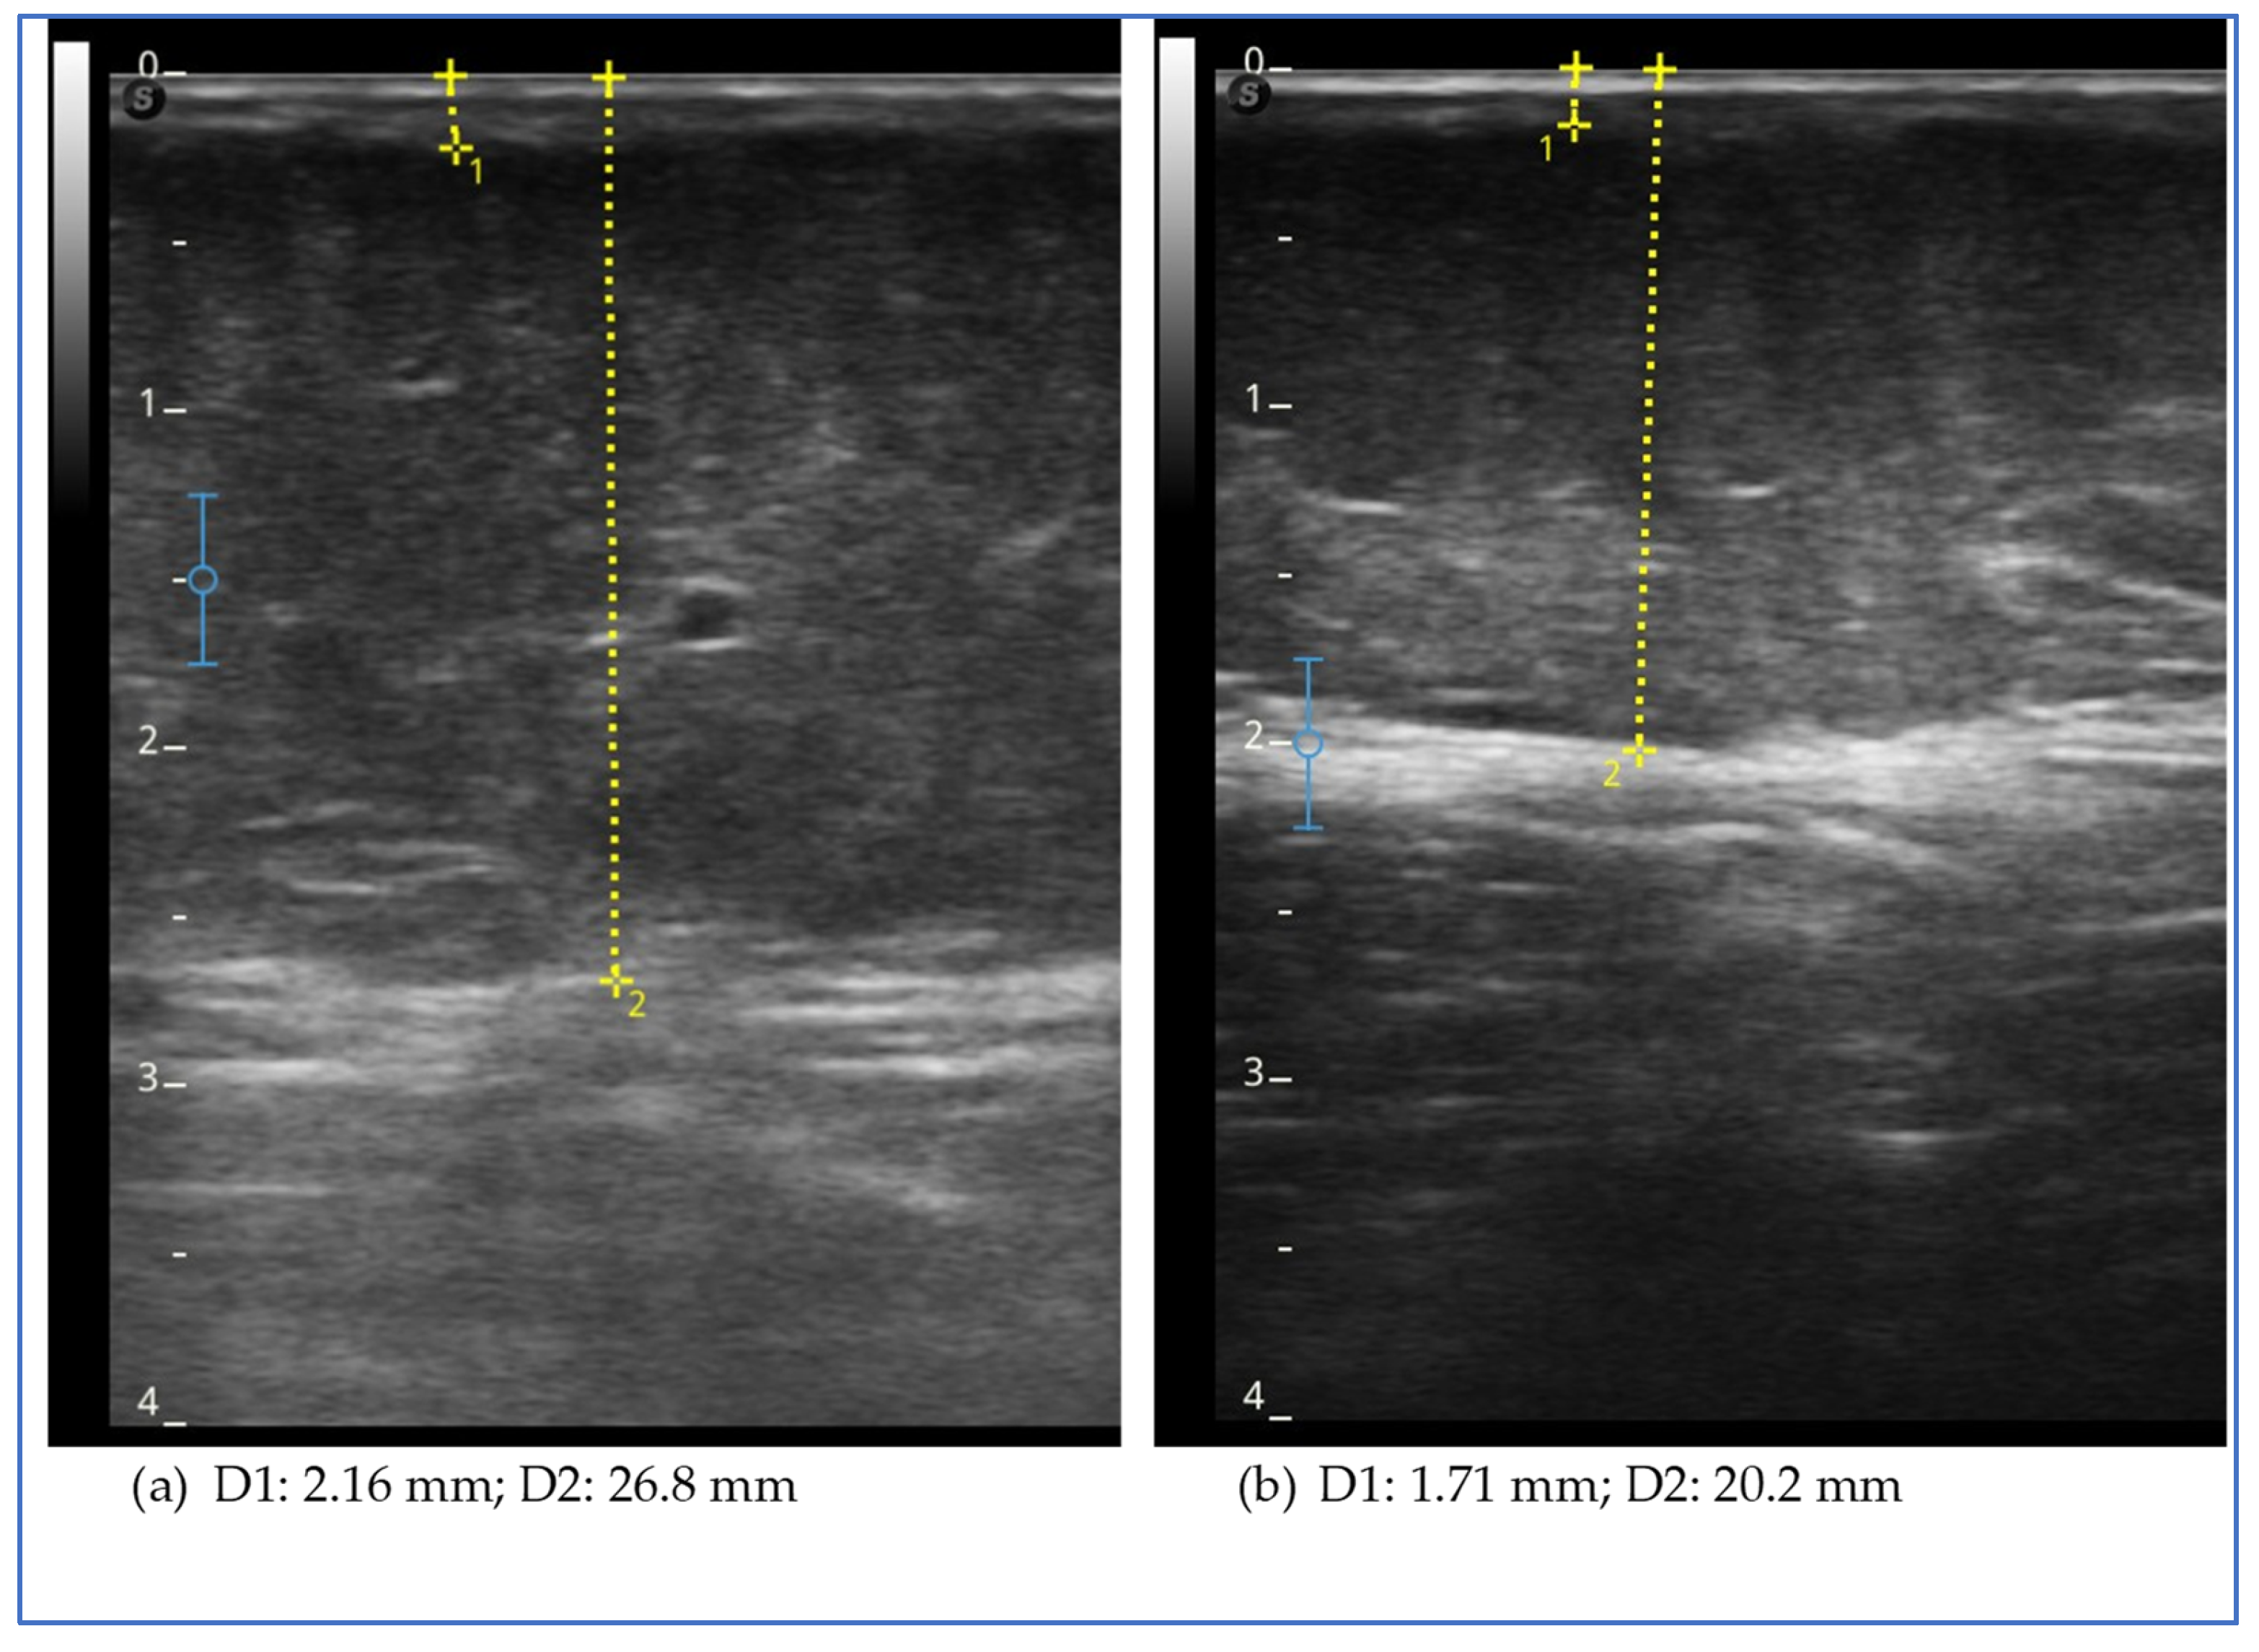

The ultrasound evaluation showed a reduction in the thickness of the subcutaneous adipose tissue in all sites assessed of the lower and upper limbs and lower abdomen, with the exception of the lower lateral third of the leg (Figure 3).

The figure shows the ultrasound measurements at the beginning of the study (a) and at the end of the study (b) for case report 3. The images refer to the upper lateral third of the leg. The yellow dotted line represents the measurement of the thickness of the skin, which includes the dermal and epidermal layers (D1), and of the subcutaneous adipose tissue (D2), which includes all the tissue from the skin to the muscular fascia.

An ultrasound evaluation revealed a reduction in the thickness of the subcutaneous adipose tissue at all assessed levels of the lower limb and upper limb and abdomen, except for the medial upper third of the leg. The greatest reduction was observed in the medial thigh (Figure 5) and arm.

The figure shows the ultrasound measurements at the beginning of the study (a) and at the end of the study (b) for case report 5. The images refer to the medial upper third of the thigh. The yellow dotted line represents the measurement of the thickness of the skin, which includes the dermal and epidermal layers (D1), and of the subcutaneous adipose tissue (D2), which includes all the tissue from the skin to the muscular fascia.